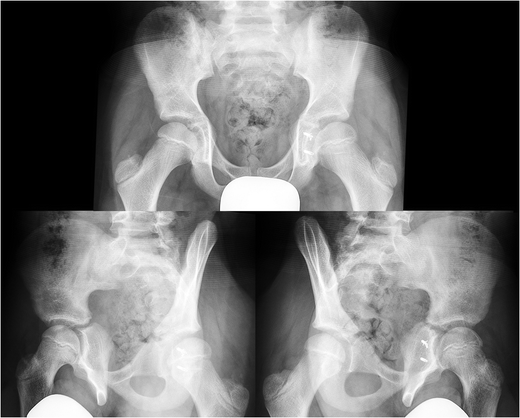

Massive heterotopic ossification associated with late ...

Banging on the wall or the floor. Two cases of a posterior wall fracture in a skeletally immature. The iliopectineal line is not disrupted but the ilioischial line may be 7 1 8.